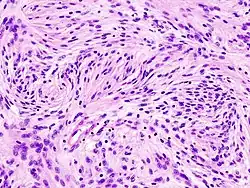

Astrocytome

Divers systèmes de catégories ont été proposés dans la littérature au fil du temps pour classer la malignité des astrocytomes. Depuis 1993, le système d'évaluation à quatre niveaux proposé par l' Organisation mondiale de la santé (OMS) est le plus largement utilisé et appliqué. Elle est basée sur quatre caractéristiques histologiques : augmentation de la densité cellulaire, mitose, prolifération endothéliale et nécrose. Par la suite, les astrocytomes de grade I, tels que les astrocytomes pilocytiques, sont généralement d'histologie bénigne. Astrocytomes II. Les grades (diffus) montrent une densité cellulaire accrue comme seule caractéristique histologique et sont des néoplasmes avec un degré d'infiltration inférieur. Les astrocytomes III montrent une mitose importante. grade (anaplasique). Et la prolifération ou la nécrose endothéliale sont observées dans les astrocytomes IV. degrés, les soi-disant glioblastomes.

Astrocytomes anaplasiques

L'astrocytome anaplasique est une tumeur cérébrale maligne caractérisée par une croissance diffuse, une densité cellulaire accrue et des figures de division nucléaire. Elle est issue d'une population cellulaire spécifique du système nerveux central, les astrocytes. Selon la classification OMS des tumeurs du système nerveux central, la tumeur correspond à une tumeur de grade III.

Les méningiomes sont les tumeurs cérébrales extrinsèques ou extra-axiales intracrâniennes les plus courantes qui proviennent des cellules de l'arachnoïde, la membrane qui recouvre le cerveau et la moelle épinière. L'incidence de cette néoplasie est d'environ 2 cas par an pour 100 000 habitants. Ils sont plus fréquents chez les femmes dans leurs sixième et septième décennies. Leur fréquence est plus élevée chez les patients atteints de neurofibromatose de type 2. La perte du chromosome 22 est caractéristique des méningiomes, bien que la signification pronostique de cette découverte soit encore incertaine.